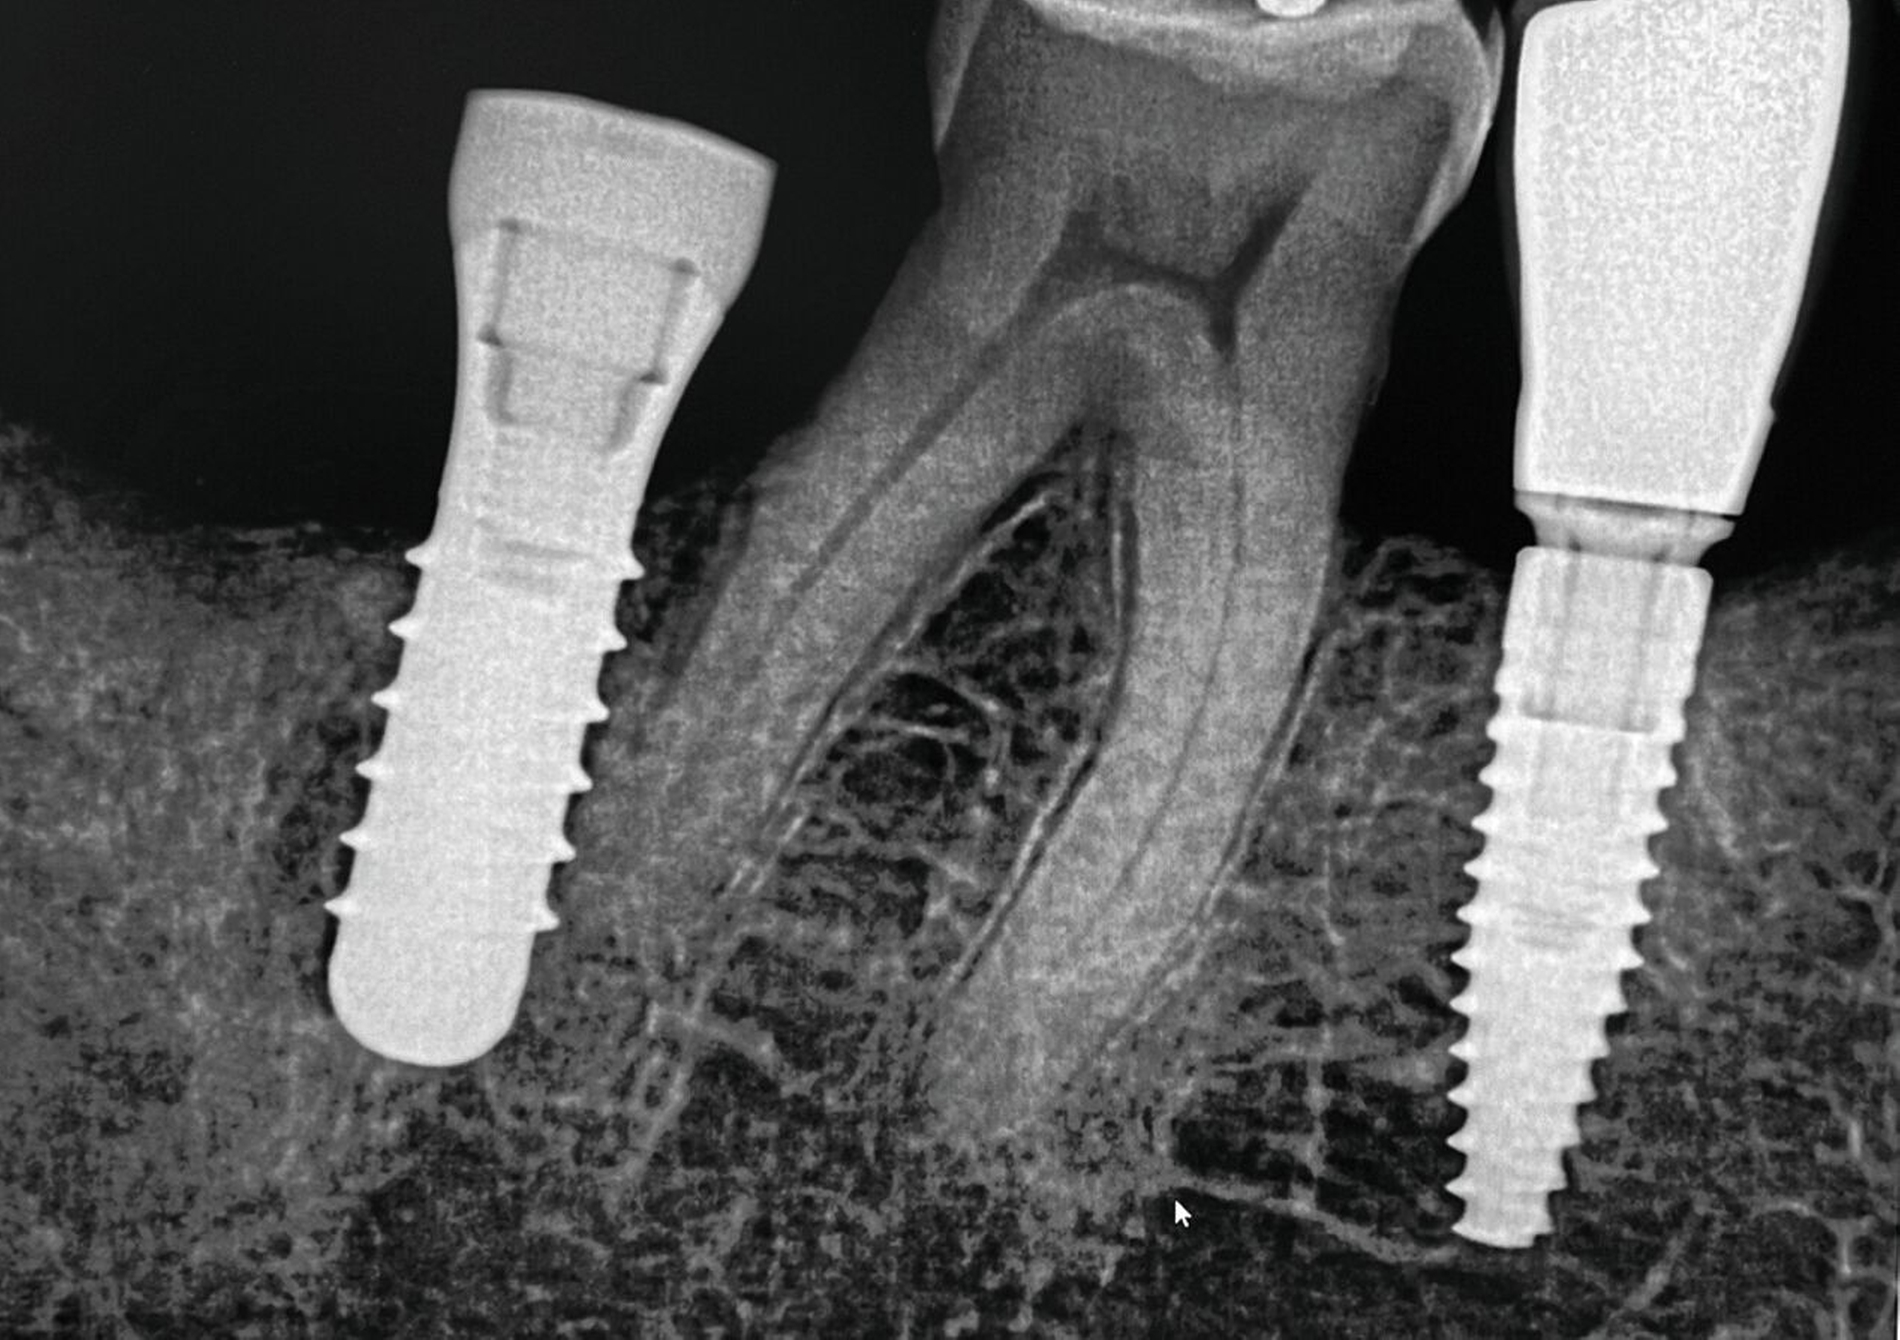

Im Implantatbereich regio 35 wurde eine abgebrochene Schraube diagnostiziert. Zum Zeitpunkt der Überweisung war die Integrität der Implantatschulter bereits kompromittiert, auch die Gewindegänge wiesen deutliche Schäden auf. Obwohl das Fragment radiologisch deutlich nach koronal überstand und somit zunächst als entfernbar erschien, zeigte sich bei der mikroskopischen Kontrolle, dass es fest auf dem Boden des Implantats aufsaß. Mehrere vorsichtige Mobilisationsversuche blieben erfolglos. Aufgrund der fortgeschrittenen Schädigung wurde das Implantat schließlich mithilfe einer passgenauen Trepanfräse entfernt und durch ein neues Implantat ersetzt (Abbildung 8).

Hier kam es zum Bruch des Gingivaformers während der Einheilphase. Das abgebrochene Schraubenfragment setzte sich im weiteren Verlauf auf dem Boden des Implantats ab. Vermutlich führte der Versuch, das Fragment mit einem Ultraschallinstrument zu mobilisieren, zu einer zusätzlichen Beschädigung des Innengewindes. Da alle konservativen Entfernungsversuche erfolglos blieben und die Wiederverwendbarkeit des Implantats nicht mehr gewährleistet war, wurde das Implantat entfernt und durch eine Neuimplantation ersetzt (Abbildung 9).